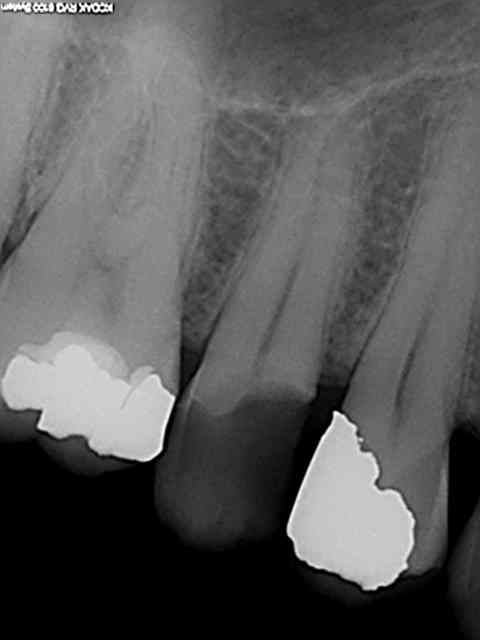

les pivotmatics sont calibrés pour 10 mm (rouge) ou 11 mm (bleu)de logement de tenon. C'est un peu emmerdant lors du mordu que le pivomatic touche l'antagoniste. Leur diamètre en outre sont supérieurs au largo 3. Ça fait des années que je procède de la sorte, les fractures de racines sont exceptionnelles contrairement aux fractures de cuspides vestibulaires ou palatines consécutives à des obturations MOD comme la 15 ci-dessus. Maintenant si tu as une technique fiable pour faire tenir des restaurations avec des pivots de 3 mm et d'un diamètre inférieur je suis preneur.)

tu aurais du y aller encore plus franco avec le largo 3, parce que là tu n'a pas réussi à peter les racines!